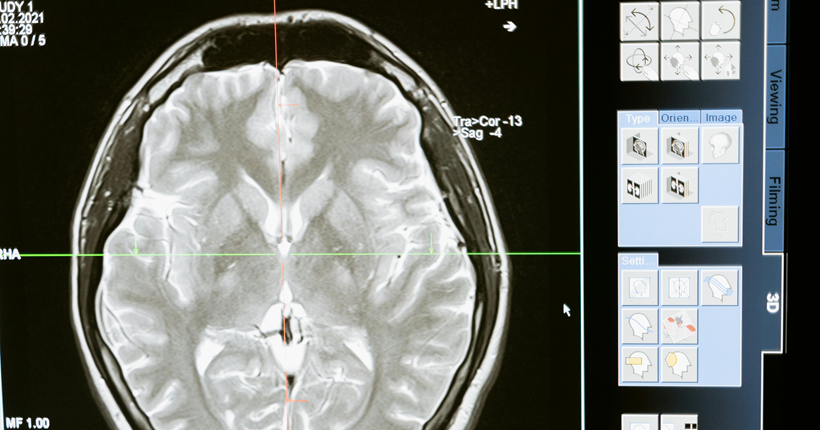

Julio Antonio Esquivel-Tamayo1, Arquímedes Montoya-Pedrón2 | 1 Doctor en Medicina. Residente de Tercer Año en Medicina Familiar. Doctorando en Ciencias Médicas. Diplomado en Medicina Natural, Tradicional y Apiterapia. Profesor Instructor. Universidad de Ciencias Médicas de Las Tunas. Policlínico Docente Manuel Fajardo Rivero. Las Tunas, Cuba. 2 Doctor en Ciencias Médicas. Especialista de Primer y Segundo Grado en Neurofisiología Clínica. Profesor e Investigador Titular. Jefe del Servicio de Neurofisología del Hospital General Dr. Juan Bruno Zayas Alfonso. Universidad de Ciencias Médicas de Santiago de Cuba. Santiago de Cuba, Cuba. La enfermedad de Alzheimer, constituye un problema sanitario y social de gran magnitud; precisa de diagnóstico y terapéutica precoces. Dispersos estudios de diversa metodología se refieren a la predicción de la demencia a partir de factores de riesgo. No obstante, existen insuficientes investigaciones que analicen en conjunto factores de riesgo y biomarcadores y los asocien; lo que ha limitado la posibilidad de acciones preventivas y terapéuticas precoces en pacientes en riesgo. Se realizó una revisión sistemática de la literatura con el objetivo de analizar los factores de riesgo y los biomarcadores de la enfermedad de Alzheimer. Se realizó una búsqueda de los términos: "demencia/ dementia", "enfermedad de Alzheimer/ Alzheimer’s disease" "factor de riesgo/ risk factor", "biomarcador/ biomarker", en las bases de datos: PubMed/Medline, Scopus, Scielo, Lilacs y mediante el buscador Google académico; se consultaron documentos no publicados. Se clasificaron los resultados de la búsqueda mediante el examen del título y resumen. De 154 investigaciones encontradas se incluyeron revisiones, metaanálisis, estudios observacionales y ensayos publicados desde el año 2017 hasta el 2023, en idioma español, inglés y portugués. Se excluyeron trabajos duplicados, libros o capítulos de libros, estudios cualitativos, que no se relacionaran con el tema o sin acceso al texto completo. Tras la aplicación de los criterios, se obtuvieron 32 estudios observacionales, 23 revisiones, 12 metaanálisis, y 3 ensayos. Se revisaron los documentos completos para verificar el cumplimiento de los criterios de inclusión. Los principales factores de riesgo encontrados son edad avanzada, menor educación, poca actividad física, hábito de fumar, consumo excesivo de alcohol, hipertensión arterial, diabetes, obesidad, depresión, pérdida o disminución de la audición, aislamiento social, los traumas craneales y la contaminación ambiental. Los biomarcadores fundamentales son: los marcadores que se utilizan en los estudios de neuroimágenes como la tomografía por emisión de positrones (PET) Amiloide, PET tau, PET con fluorodesoxiglucosa (FDG); y en líquido cefaloraquídeo y plasma: Aβ42, Aβ42/Aβ40, p tau 217, p tau 181, proteína gliofibrilar ácida (GFAP), y neurofilamentos de cadena ligeras. Se reconoció el uso de los parámetros cuantificados en el P300 como biomarcadores complementarios clasificadores de la presencia y del nivel de disfunción cognitiva de etiología enfermedad de Alzheimer posible. La mayoría de los estudios analizados, aunque abordan con profundidad la relación de los factores de riesgo y la enfermedad de Alzheimer, tienen limitaciones al asociar unos factores con otros, o con biomarcadores. Se requieren estudios longitudinales, a partir de la presencia de los factores de riesgo asociados a biomarcador, desde edades pregeriátricas en pacientes sanos, que tengan como salidas el deterioro cognitivo y el desarrollo de la demencia, para construir un modelo de predicción. Leer el artículo completo